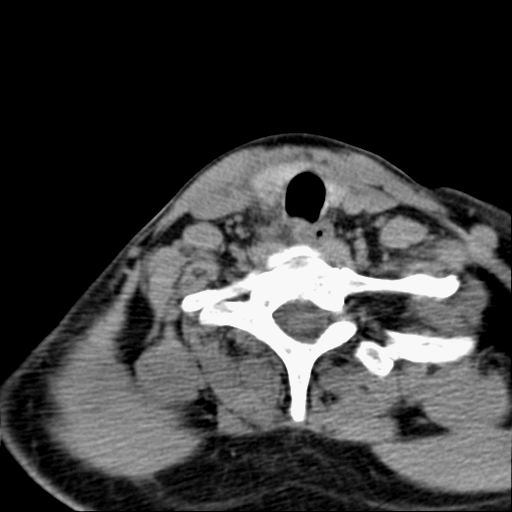

标题: CT23947 右颈部触及00.5x1.5cm质硬长形肿块,疼痛 [打印本页]

标题: CT23947 右颈部触及00.5x1.5cm质硬长形肿块,疼痛

右侧甲状腺腺瘤考虑

甲状腺癌可疑

右侧甲状腺病灶,建议增强或结合b超检查。

右甲状腺占位,建议增强。

甲状腺右叶占位病变,建议增强扫描。

甲状腺占位  定性有时很难 但无论癌还是腺瘤 还是手术比较好!以下是甲状腺占位的ct鉴别诊断

ct对甲状腺病变的诊断作用

确定病变范围,判断有无部属淋巴腺转移,甲状腺肿物没有可靠的征象鉴别良、恶性,如有部属淋巴结肿大、喉返神经麻痹、甲状软骨或其它喉软骨破坏等表现,则有利于诊断恶性。钙化不是鉴别良、恶性的依据。

1.甲状腺ca:中年妇女好发,病例分型,乳头状、滤泡状、未分化癌及髓样癌四种。

ct表现:形态不规则的软组织密度肿块,可累及部分或大部分甲状腺组织,密度不均,可坏死、囊变、钙化,增强病灶呈不均匀强化,有局部侵犯或转移时可有颈部淋巴结肿大。

2.甲状腺腺瘤;常见的良性肿瘤,病理分型:滤泡状腺瘤、乳头状囊性腺瘤,以前者多见,腺瘤周围有完整的包膜,患者大多为中青年女性,大部分无任何临床症状。

ct表现肿瘤呈稍低密度结节状肿块,边缘光整、锐利病灶均匀强化,少数腺瘤可有钙化。

甲状腺右侧叶占位,定性困难,建议增强。

右侧甲状腺低密度病灶,性质待定;建议行进一步检查。